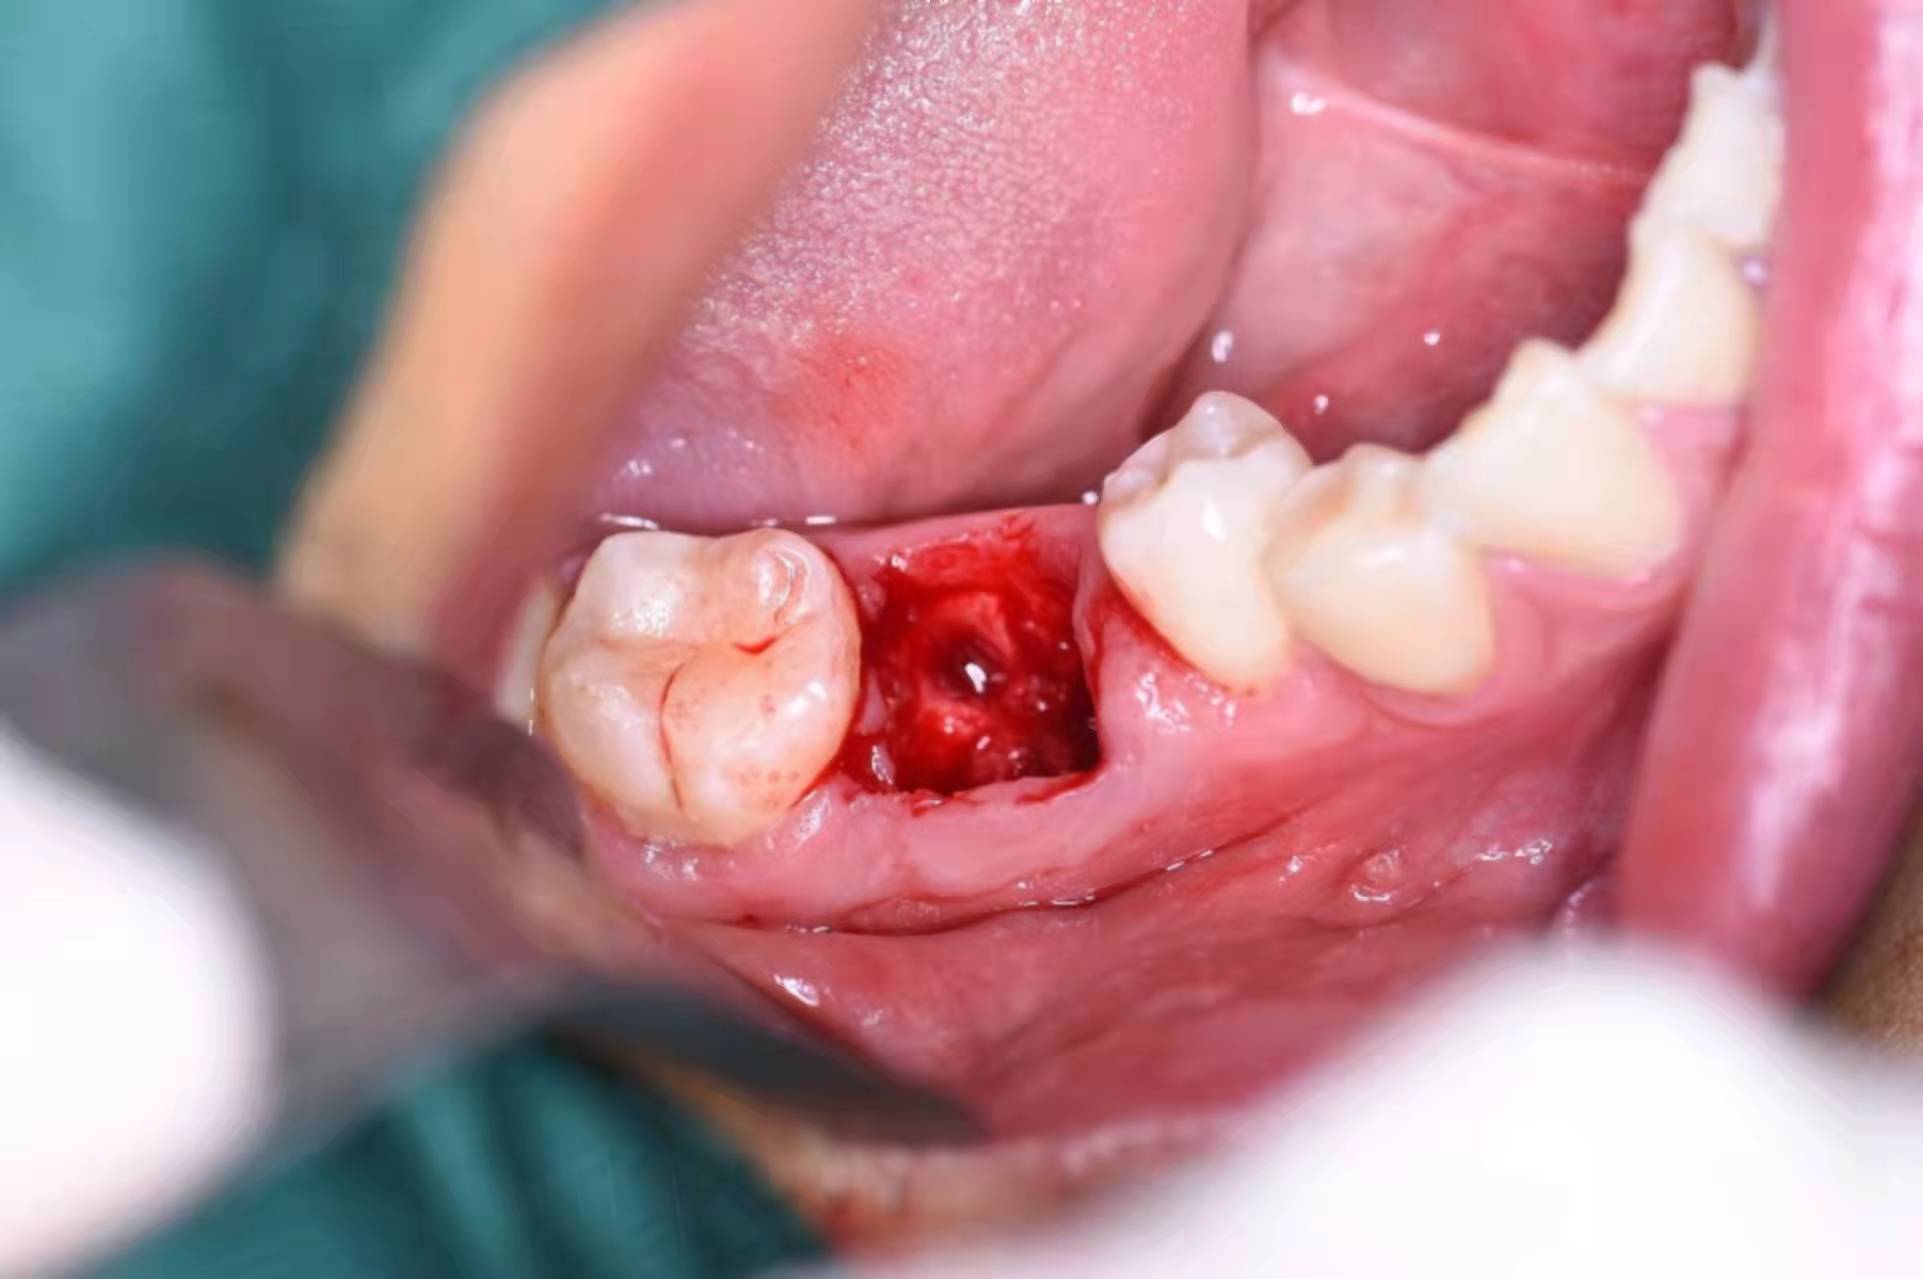

拔下來的殘根,全部拿出:

備洞,準(zhǔn)備植入種植體